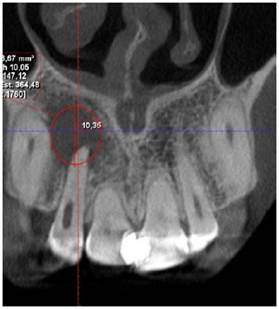

Se realiza el segundo control tomográfico en fecha 11 de noviembre de 2023 donde el tamaño del quiste en sentido longitudinal es de 10,35 mm y en sentido transversal de 7,95 mm (Figura 5a y 5b), observando una reducción considerable del quiste se decide realizar la segunda intervención quirúrgica, donde se hizo la enucleación del quiste y extracción de la pieza 1.2, esta presentaba dos perforaciones laterales y fue valorada previamente por endodoncia, que indico la extracción de la pieza y realizaron las endodoncias de las piezas 1,1 y 1,3 por la cercanía a la lesión quística.

Figura 5a Tomografía 11/11/2023, se observa neoformación ósea alrededor de la lesión y una disminución en la altura a 10,35 mm.

Figura 5b Tomografía corte axial 11/11/2023, se observa neoformación ósea alrededor de la lesión y disminución del ancho de la misma a 7,95 mm.